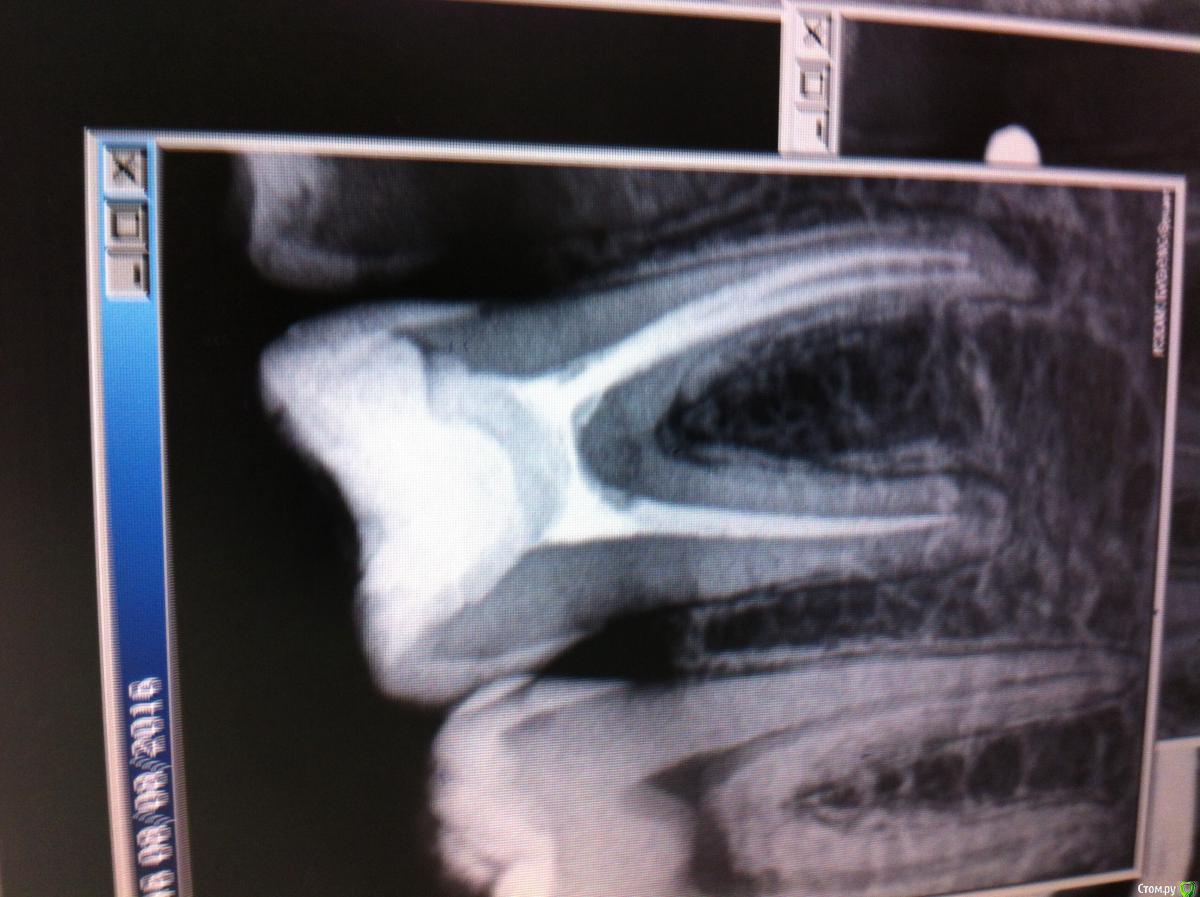

Girl Опубликовано 9 октября, 2016 Поделиться Опубликовано 9 октября, 2016 Добрый день, коллеги. . Подскажите, как возможно провести эндодонтию в такой ситуации? Какие способы используете? Или это проходить вслепую только возможно? Ссылка на комментарий